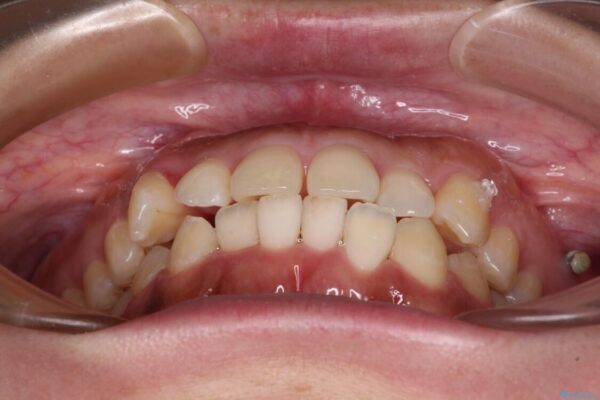

治療後について

カリエールディスタライザーを併用したことで、すっきりとした口元になり、上下の正中を合わせることができました。

治療後

• 【モニター】カリエール・ディスタライザーを併用した八重歯のインビザライン矯正 治療後画像